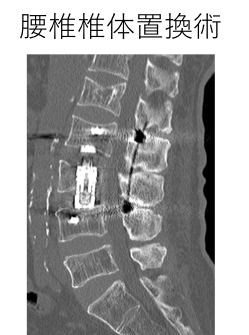

腰椎椎間板ヘルニア、腰部脊柱管狭窄症、成人脊柱変形(側彎症、後彎症)、により坐骨神経痛などを代表とする下肢の神経症状が出現します。まずは内服薬による治療から開始しますが、痛みの症状が強い場合には硬膜外ブロックや神経根ブロックなどを行います。それでも症状が寛解しない場合には、筋層を温存してなおかつ効果が長く持続する棘突起縦割椎弓形成術から、側方から後腹膜腔を経由して脊椎の前方から固定を行う椎体置換術やOLIF、後方からのPLIF、TLIFなどの固定方法を患者さんごとに使い分けて最善の治療を目指します。

腰椎後方固定術 腰椎椎体置換術